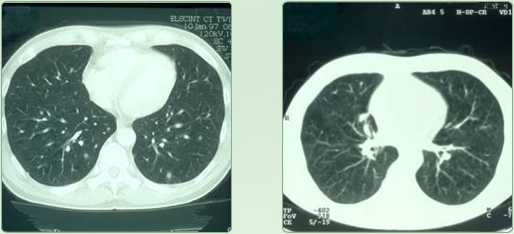

Lungenmetastasen vor RTH - Lungenmetastasen nach RTH

Bronchial - CA

diffuse Lungenmetastasierung eines mucinösen Adeno - CA - s unklaren Ursprungs (CUP-Syndrom) ED 1/97 2 malige Regionale Chemotherapie in Kombination mit 12 Behandlungen regionaler Tiefenhyperthermie (3 x / Woche) führten zur Vollremission; aus

Mastall H. Zeit- und situatiosgerechte Einsatzmodelle für komplementäre Verfahren während

konventionell-onkologischer Therapien.

32. Medizinische Woche Baden-Baden 1998; 02.XI

Lungenmetastasen vor OP

Lungenmetastase eines Dickdarm - CA's ( ED 11/97 ). Präoperative 2 malige Behandlung der Lungenmetastase mit Regionaler Tiefenhyerthermie

Ergebnis:

Die postoperative Aufarbeitung des Tumors ergab eine 70 % ige Nekrose (Zelltod) der

Lungenmetastase; aus